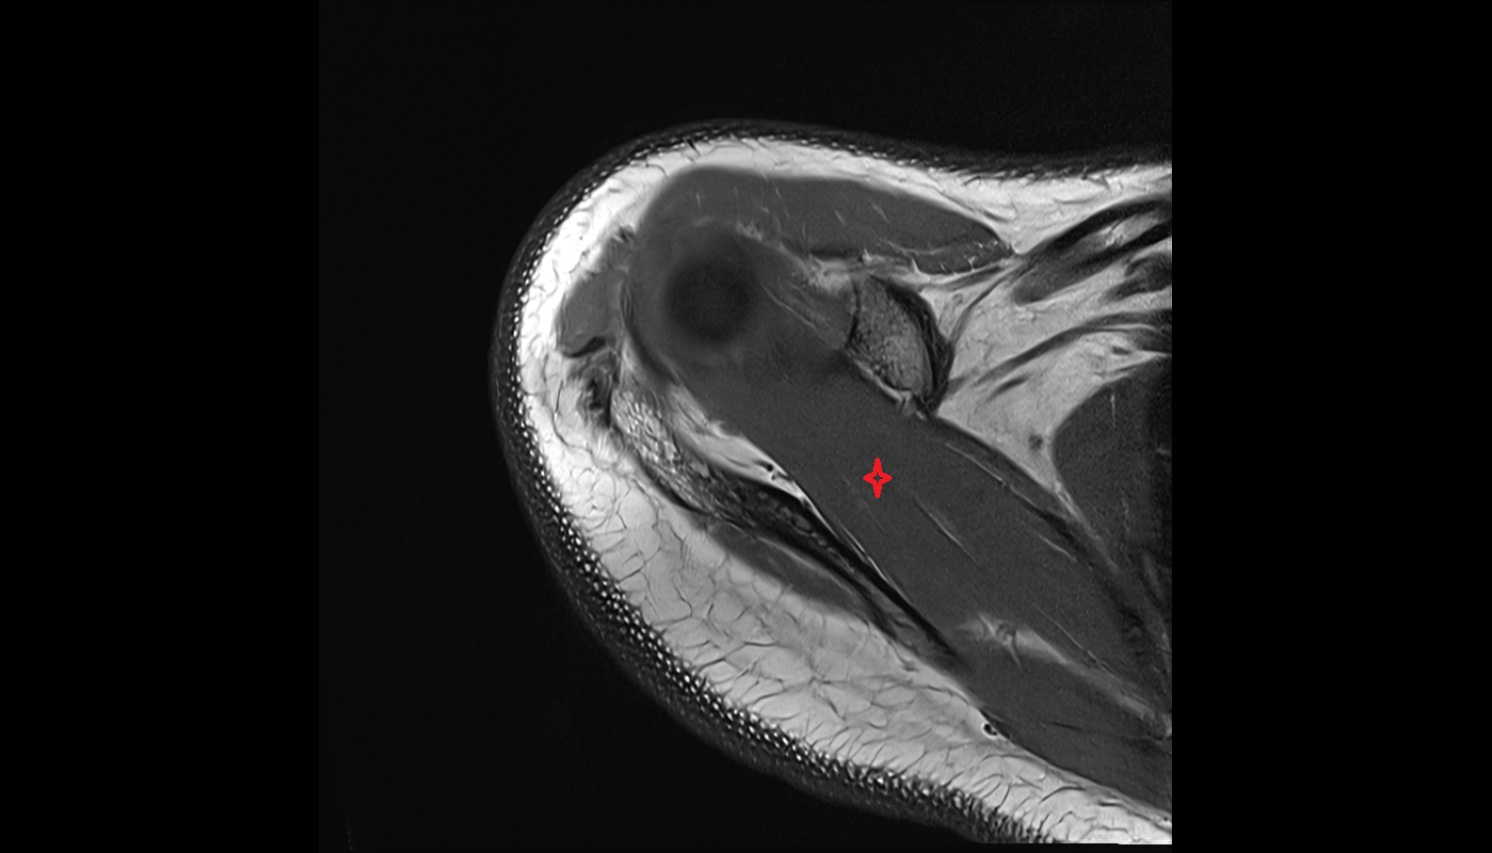

- Temporomandibular joint

- Articular disc of temporomandibular joint

- Mandibular condyle

- Mandibular fossa